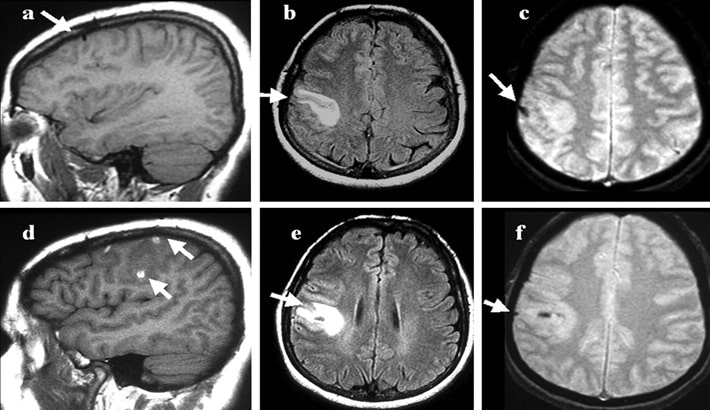

تومورهای اولیه مغز در سی تی اسکن

تومورهای اولیه مغز، مستقیماً از بافتهای مغزی منشاء میگیرند. سی تی اسکن مغز میتواند بسیاری از آنها را بهوضوح نشان دهد.

از جمله تومورهایی که در تصاویر سی تی قابل تشخیص هستند میتوان به گلیوما، آستروسیتوما، مننژیوم و مدولوبلاستوما اشاره کرد. این تومورها معمولاً تفاوت چگالی با بافت طبیعی مغز دارند و در تصاویر، بهصورت نواحی روشن یا تیره دیده میشوند.

در برخی موارد، برای مشاهده بهتر از سی تی اسکن مغز با تزریق ماده حاجب استفاده میشود. این تزریق باعث افزایش کنتراست تصاویر میشود و به رادیولوژیست کمک میکند که حتی تومورهای کوچک را نیز تشخیص دهد.

تفاوت تومورها در تصاویر سی تی اسکن مغز

تومورها در سی تی اسکن مغز بسته به نوع، محل و میزان رشدشان ظاهر متفاوتی دارند. برخی از تومورها جامد و برخی دارای بخشهای کیستی هستند. تومورهایی مانند مننژیوم معمولاً مرز مشخصی دارند؛ در حالیکه گلیوماها گاهی مرز مشخصی نداشته و در بافت مغز نفوذ میکنند. استفاده از سی تی اسکن مغز با تزریق، در این مواقع کمک میکند تا حدود تومور دقیقتر مشخص شود.